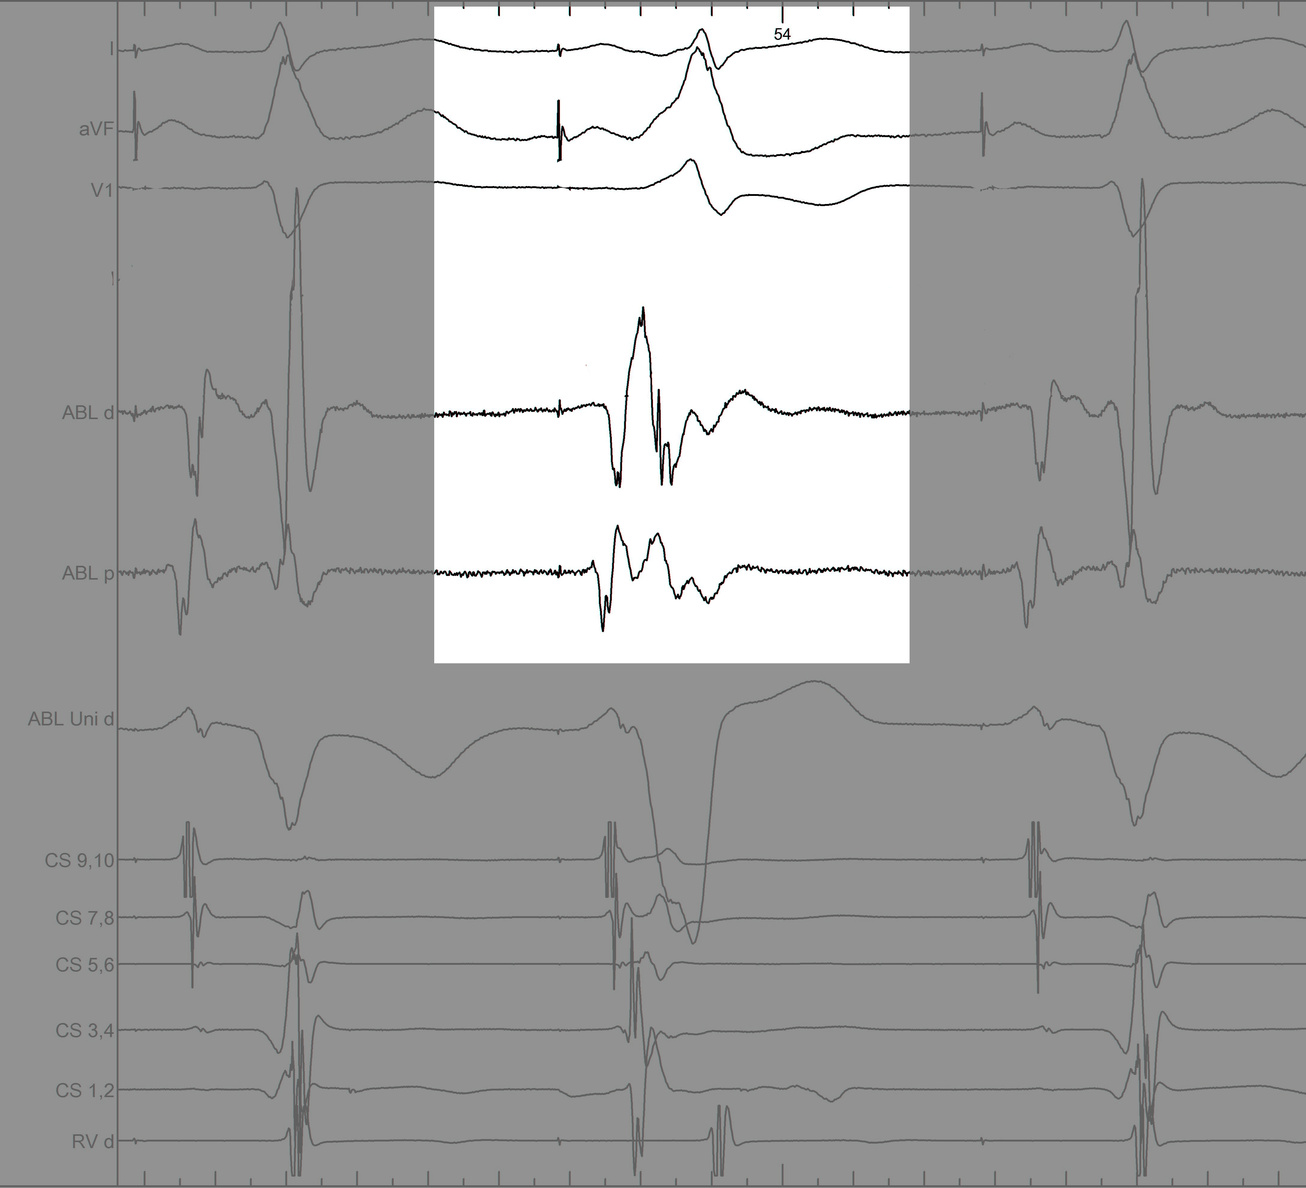

#4 Key to mapping is to identify signal components

mask1.jpg

mask2.jpg

mask3.jpg

mask4.jpg

pseudo_disappearance.jpg